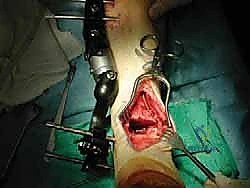

Intraoperative Execution: Granular Steps

1. Débridement and Distraction of the Ankle Joint

Now that we have excellent exposure, our first intraoperative task is to prepare the recipient bed.

- Synovectomy: Through our anterior capsulotomy, we gain access to the joint. Our first task is a meticulous débridement. Using a Cobb elevator and small rongeurs, carefully excise all inflamed synovium. Observe the hypertrophic synovial tissue, often a significant pain generator. This thorough synovectomy is crucial for both pain relief and to facilitate proper seating of our allograft later.

- Osteophyte Removal: Next, with a fine osteotome and a mallet, gently remove any anterior or posterior osteophytes that are impinging on motion or hindering our access. Ensure you have a clear view of the entire tibiotalar articulation.

- External Fixator Application for Distraction: Now, let's apply our external fixator. We use a standard distraction device to symmetrically open the joint.

2. Recipient Tibial and Talar Cuts

Now, with the joint adequately distracted, we proceed with preparing the recipient bone beds. We'll use the Agility cutting block system for precision.

- Templating and Cutting Block Placement: Based on our preoperative templating, select the appropriate size Agility ankle arthroplasty cutting block.

* Fluoroscopic Confirmation: Before making any cuts, confirm the placement and size of the cutting block with intraoperative fluoroscopy in AP, lateral, and mortise views. This is a non-negotiable step to ensure accuracy and prevent malalignment.